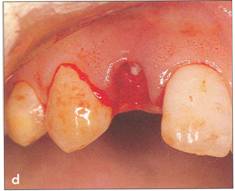

Fi 545e45f g 5-5b Incision and reflection of the gingival flap. The incision is made in the gingival sulcus around the tooth at the recipient site and the donor tooth. Vertical incision is made in the distobuccal corner of the first molar. Horizontal incision is made in the buccal corners of the donor tooth and the gingival flap is reflected. |

Fi 545e45f g 5-5c After extraction of the second molarfrom the recipient site. |

Fi 545e45f g 5-5d Extraction of the donor tooth. |

Fi 545e45f g 5.5e The donor tooth. |

Fi 545e45f g 5.5f After modification of the recipient site. |

Fi 545e45f g 5-59 Try-in of the donor tooth. |

Fi 545e45f g 5-5h Releasing incision of the flap. The releasing incision is made in the lingual gingival tissue of the extraction socket of the third molar to achieve better fit of the gingival flap. Fi 545e45f g 5-5i Suture of gingival flap. Before transplantation of the donor tooth, the flap of the horizontal incision and the area of the mesial proximal wall are sutured. One end of each suture is left at 30 mm while the other end of the suture is left uncut. |

Fi 545e45f g 5-5j Plantation of the donor tooth. The donor tooth is sealed tightly by the gingival flap because of the flap's elasticity. |

Fi 545e45f g 5-5k Fi 545e45f xation of the donor tooth by the sutures. The extra suture is used for fixation of the donor tooth. Extra periosteal suturing of the distolingual area is used for fixation. |

Fi 545e45f g 5-51 After application of the surgical dressing to protect the surgical area. |